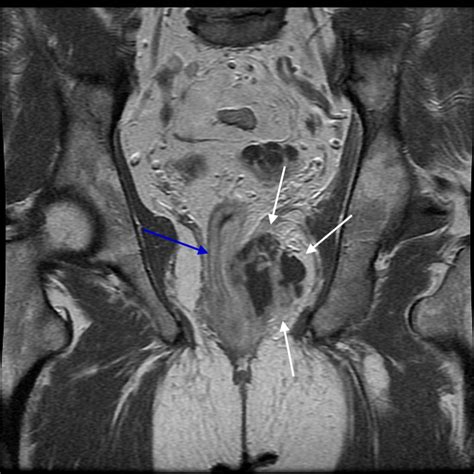

Diagnosing a perianal abscess typically involves a physical examination by a healthcare provider. In some cases, additional tests may be necessary to confirm the diagnosis and rule out other conditions. Abscess perianal pictures can be particularly helpful in visualizing the abscess and determining the extent of the infection.

• Order imaging tests, such as an ultrasound or MRI, to get a clearer view of the abscess.